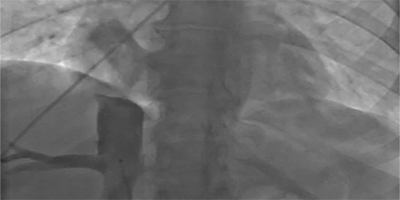

Successful Biventricular Pacemaker Implantation via Right Iliac Vein Route

See Videos